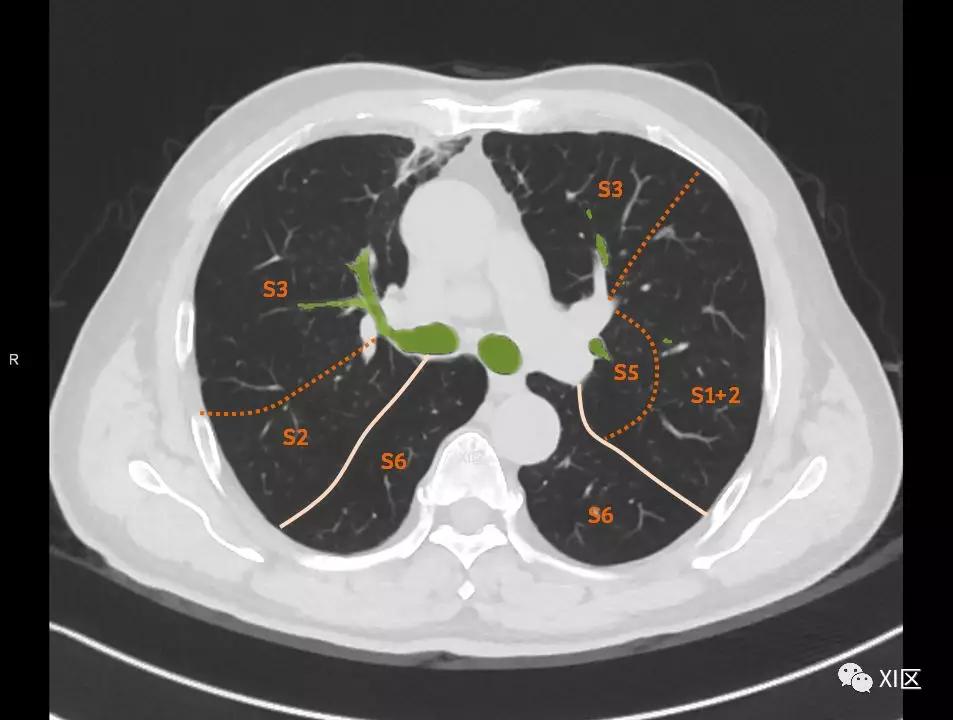

肺的断层分段示意图

在进行肺的分段时,可以上下观察浏览,沿着相应气管的走形可以更容易准确地进行分段。